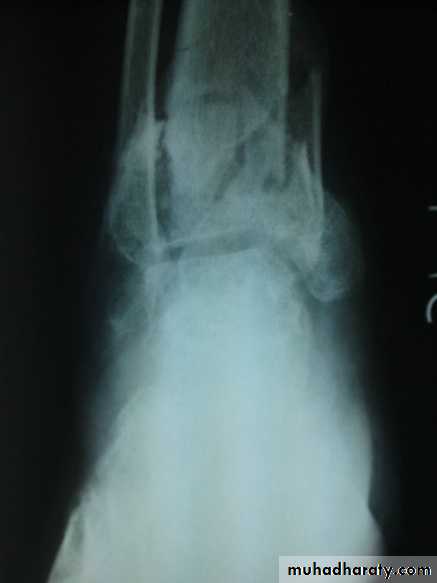

Zakho hospital Orthopedics Dr. MuthanaComminuted fractures of the tibial plafond (Pilon fracture)

Severe axial compression of the ankle (FFH).Shattering of ankle joint surface.

Secondary Osteoarthritis is common.